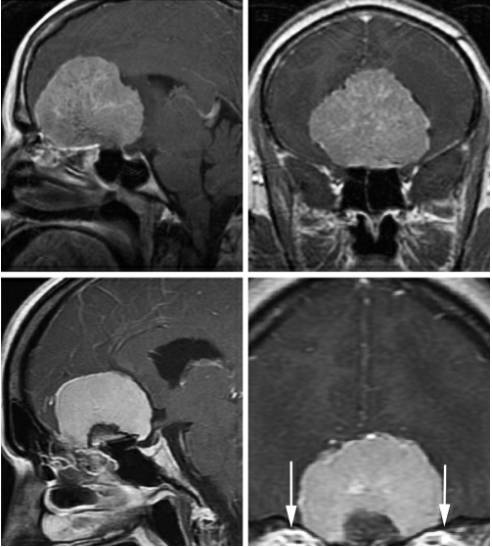

图1. 跨越视神经的(上图)大型的嗅沟脑膜瘤(OGM)最适合开颅手术。如果在冠状位MRI图像上(下图),肿瘤没有明显的超过眼眶的中线(眶中线平面,白色箭头)或者达到视神经外侧,经鼻内镜入路是合适的。

如果肿瘤大部分位于鼻窦内,手术计划应该考虑双侧额叶开颅,或是分期最大限度切除肿瘤。由于嗅沟脑膜瘤是一种生长较慢的良性肿瘤,笔者通常不会激进的去切除位于窦内的少许肿瘤组织。

经鼻切除巨大肿瘤,即使是经验丰富的医生,也需要很长的手术时间,因此需要分期进行。笔者认为这些大的或者巨大的肿瘤经鼻分期切除并不能带给病人最大的利益,经翼点入路一次性切除肿瘤更为合适。